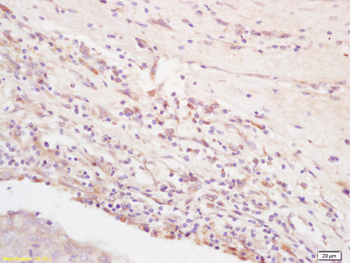

Integrin Alpha V Rabbit Polyclonal Antibody抗体

Integrin Alpha V Rabbit Polyclonal Antibody

ITGAV

IF, IHC-Fr, IHC-P, IP, WB

KLH conjugated synthetic peptide derived from human Integrin Alpha V

应用稀释比例:WB=1:500-2000, IHC-P=1:100-500, IHC-F=1:100-500, IF=1:100-500, IP=1:20-50